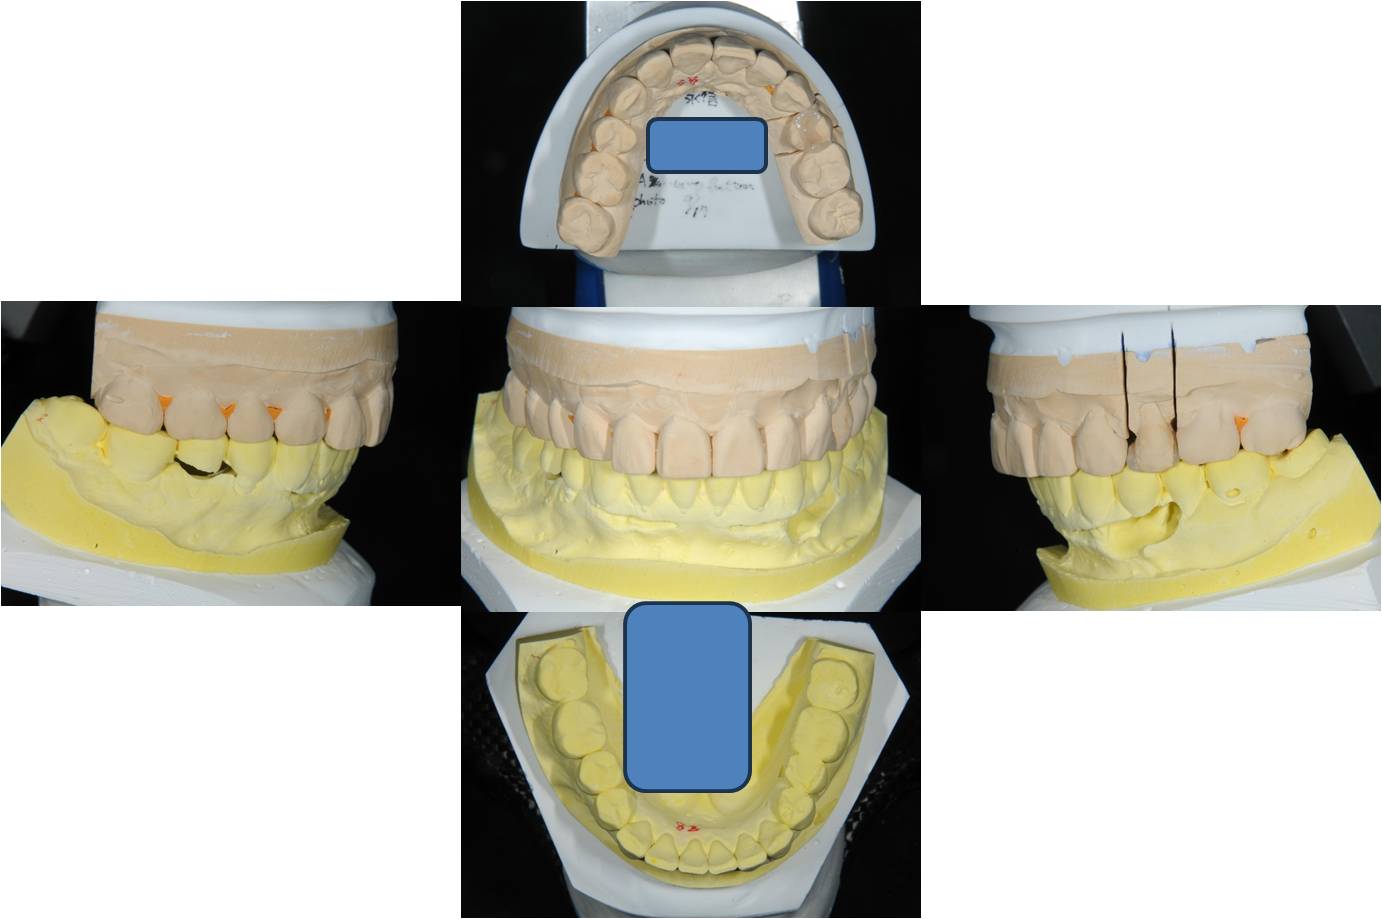

模型上咬合器

模型上製作陶瓷崁體